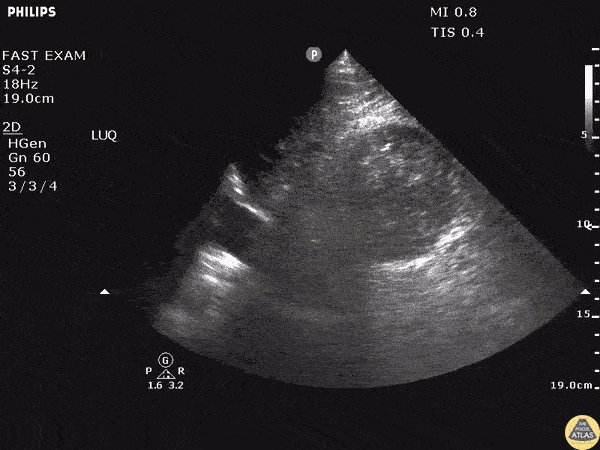

A young male presented to the ED following a 20 foot fall. He presented with LUQ pain, left flank pain, and soft vitals. FAST exam showed no fluid in Morison’s pouch or in the pelvis but revealed a large, left-sided, retroperitoneal hematoma noted by the distortion of the left kidney. Image courtesy of Robert Jones DO, FACEP @RJonesSonoEM Director, Emergency Ultrasound; MetroHealth Medical Center; Professor, Case Western Reserve Medical School, Cleveland, OH View his original post here